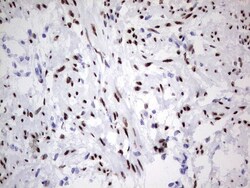

- Submitted by

- Invitrogen Antibodies (provider)

- Main image

- Experimental details

- Immunohistochemical staining of paraffin-embedded human endometrium tissue within the normal limits using anti-PGR mouse monoclonal antibody. (Heat-induced epitope retrieval by 1 mM EDTA in 10mM Tris, pH8.5, 120°C for 3min, TA805108)